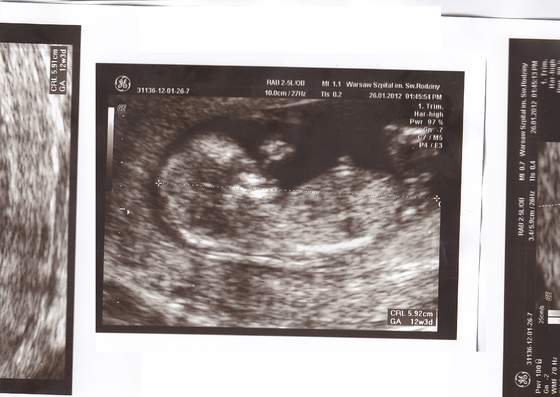

, ale to dopiero 17.02 będzie pierwsze podejście....

Partner będzie mógł być tak czy siak, niezależnie od rodzaju USG.